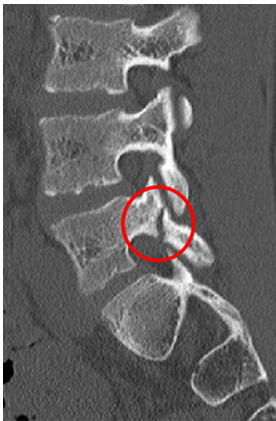

発育期に発生する関節突起間部(上関節突起と下関節突起の間 上図の赤丸の部分)で発生する疲労骨折

MRIで疲労骨折を確認し、成長期腰椎分離症の診断ができたら、つぎにCTで病期の診断をします。